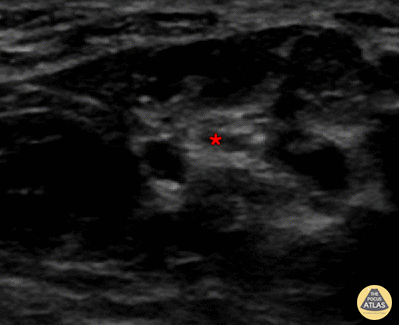

In-plane median nerve block at the wrist, with needle seen entering from screen right, with anesthetic deposited adjacent to median nerve (*). Denver Health Ultrasound Fellowship